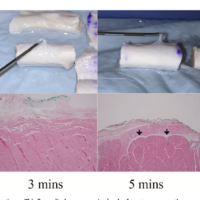

EULAR-OMERACTスコアとは何か

今回の研究で用いられているのが、EULAR-OMERACTスコアと呼ばれる評価方法です。

これはエコー画像をもとに滑膜炎の程度を0から3の4段階で評価する標準化された方法です。

グレースケール(GS)は滑膜の厚みを評価し、ドプラ(PD)は血流、すなわち炎症の強さを評価します。この2つを組み合わせることで、関節リウマチの状態を客観的かつ詳細に把握することが可能となります。

本研究では、経験の異なる医師が同じエコー画像を評価した場合の一致率が検討されています。その結果、評価の一致率は0.72から0.97と非常に高い値を示しました。

これは、適切なトレーニングを受ければ、誰が評価しても同様の結果が得られることを意味します。

臨床症状と強く関連する

さらに、エコーで評価した炎症の程度は、DAS28などの臨床指標と中等度から高い相関を示しました(相関係数0.57から0.79)。